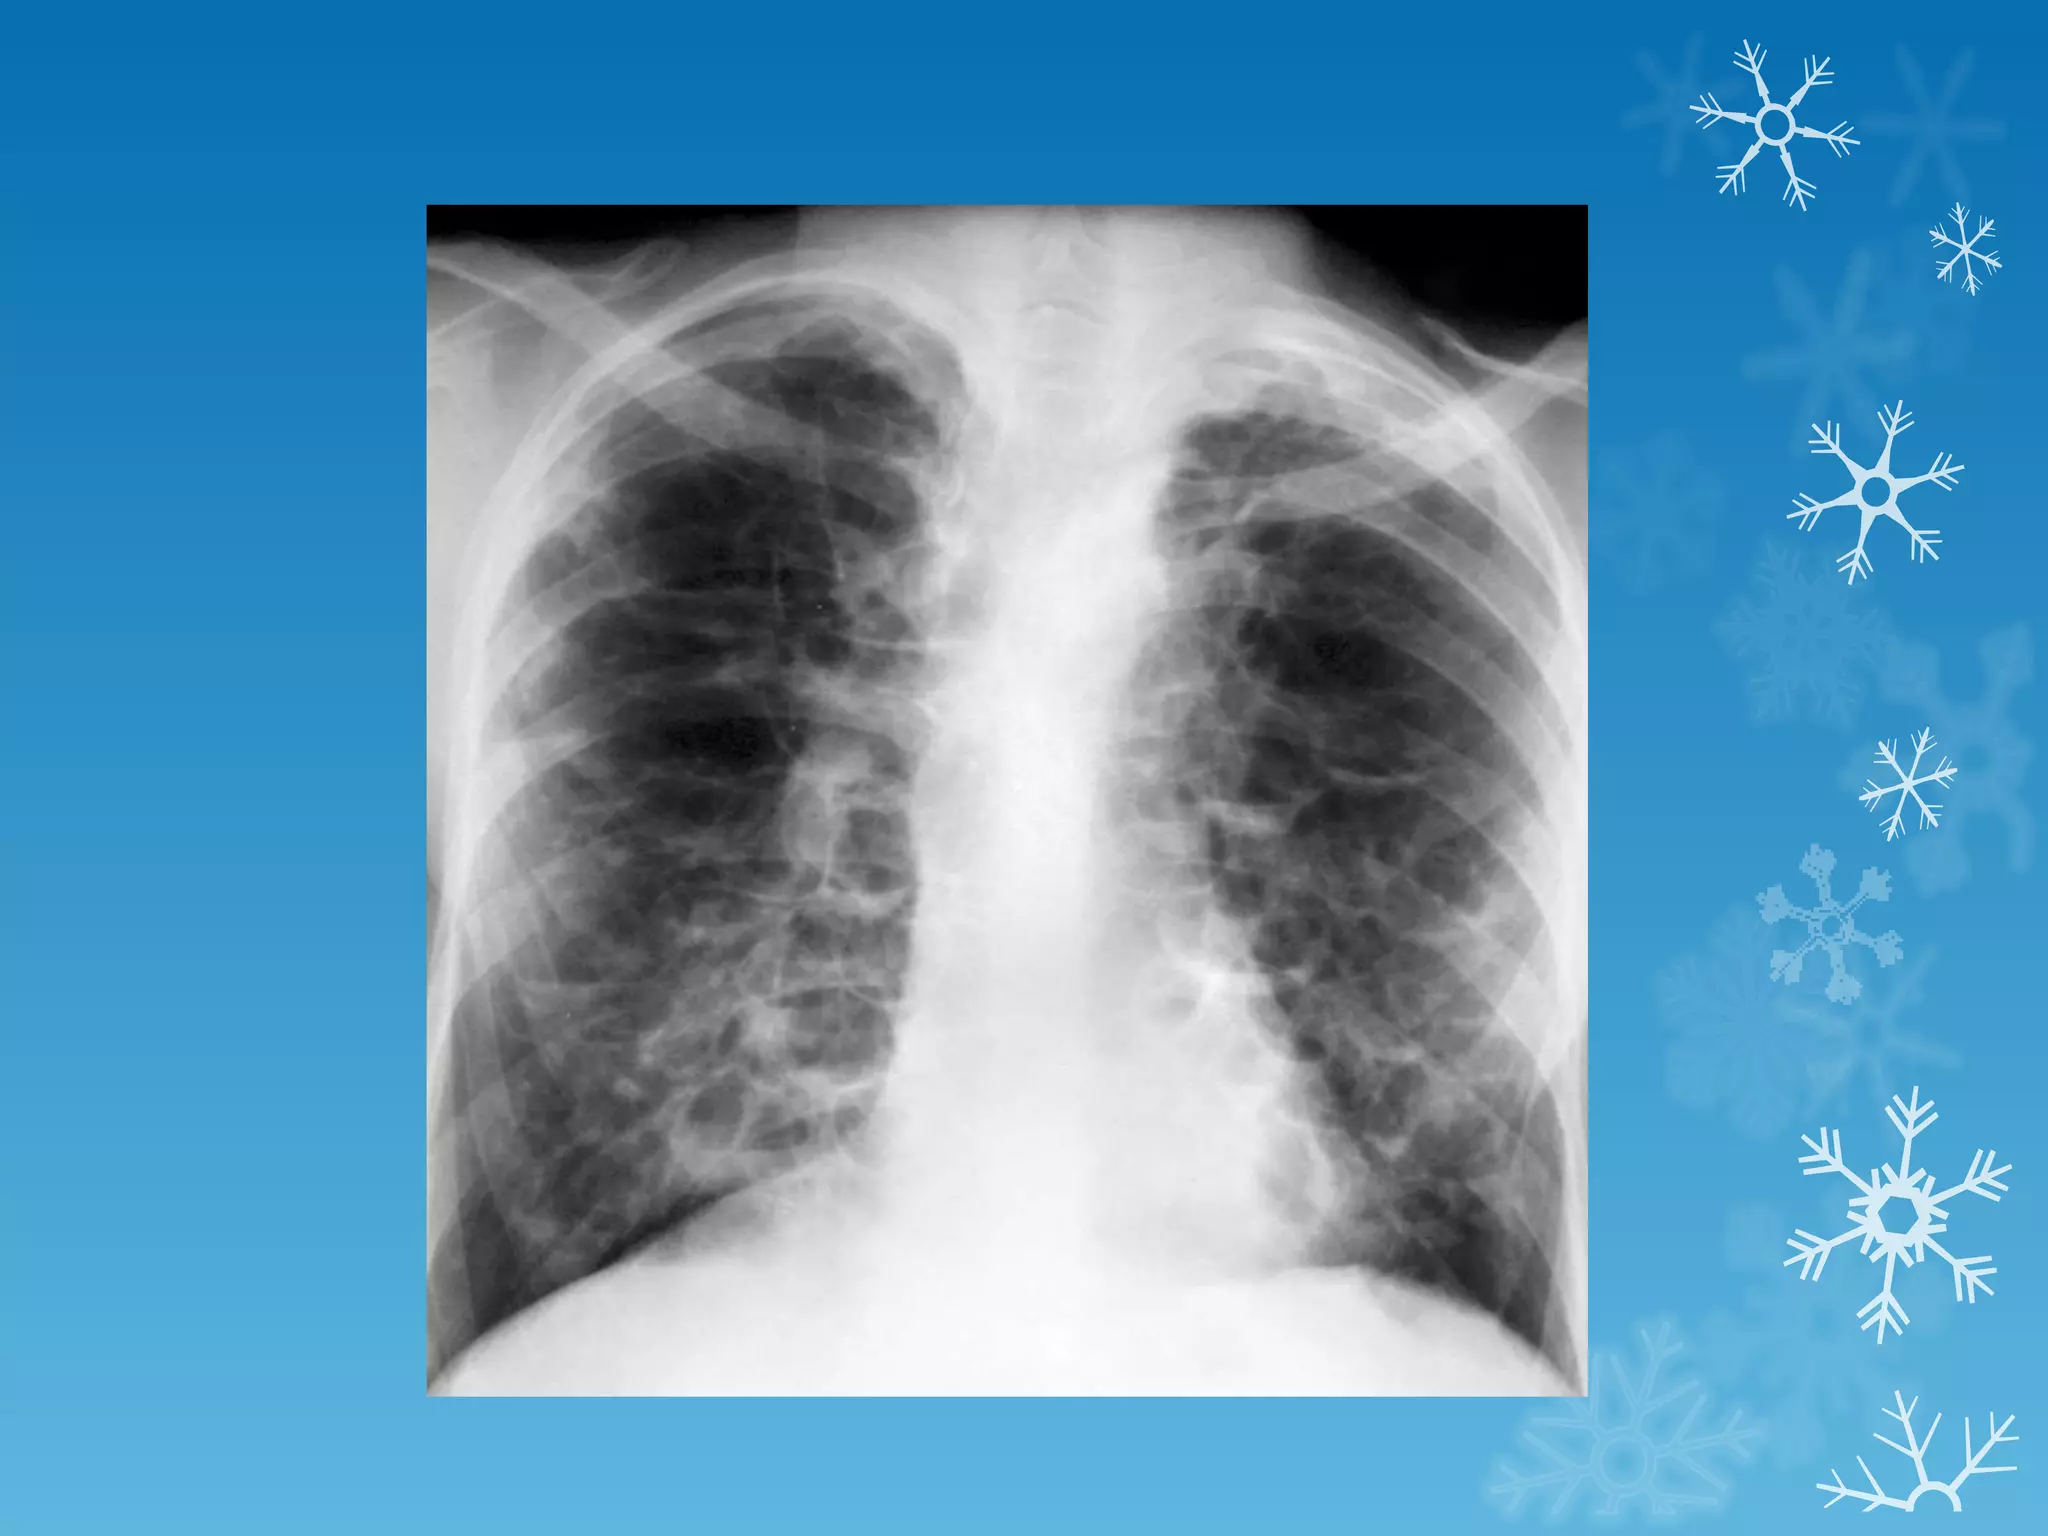

This document discusses chest x-ray interpretation and provides guidance on evaluating x-rays. It explains that tissue density determines how an x-ray beam penetrates, with denser tissues appearing whiter and less dense tissues appearing blacker. It also outlines different chest x-ray views and factors to consider like patient orientation, age, gender, and rotation. Abnormalities are described as appearing too white, too black, too large, or in the wrong place. The document stresses a systematic approach of identifying, localizing, describing lesions, and providing differential diagnoses.